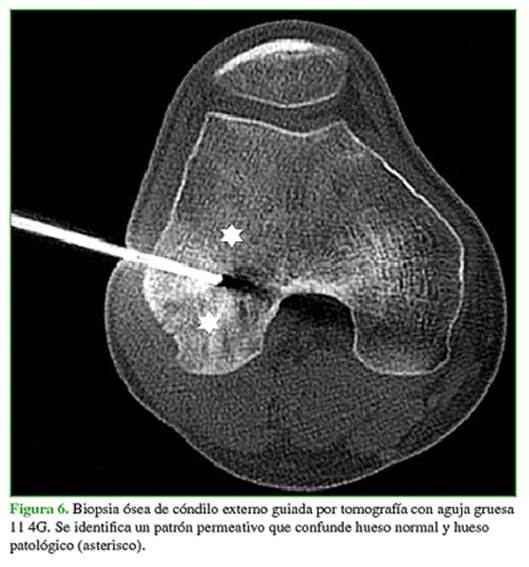

Posteriormente y sabiendo que se trataba de una única lesión, el Comité de Tumores decide realizar una biopsia guiada por tomografía (Figura 6). El estudio anatomopatológico informó una infiltración linfoide a nivel intertrabecular y marcados fenómenos de atricción celular, con inmunohistoquímica positiva para CD20, CD10 y Bcl6, y un alto índice de proliferación (ki67).